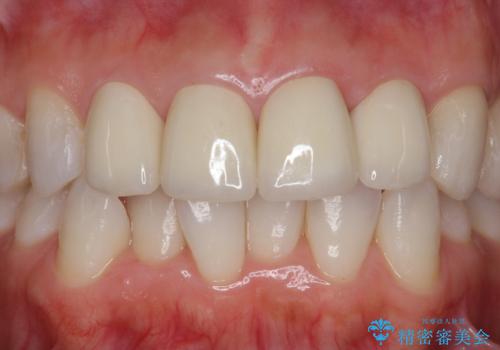

また、色を決める前にホワイトニングを行い、全体的に歯を白くしてから色を決めました。

- 51.7万円(ジルコニアクラウンスタンダード 10万円x4本、仮歯1万円x4本 オフィスホワイトニングエクセレント 3万円x1回)費用は治療当時の料金となります

色や形については納得いくまで修正し、最後は満足されていました。